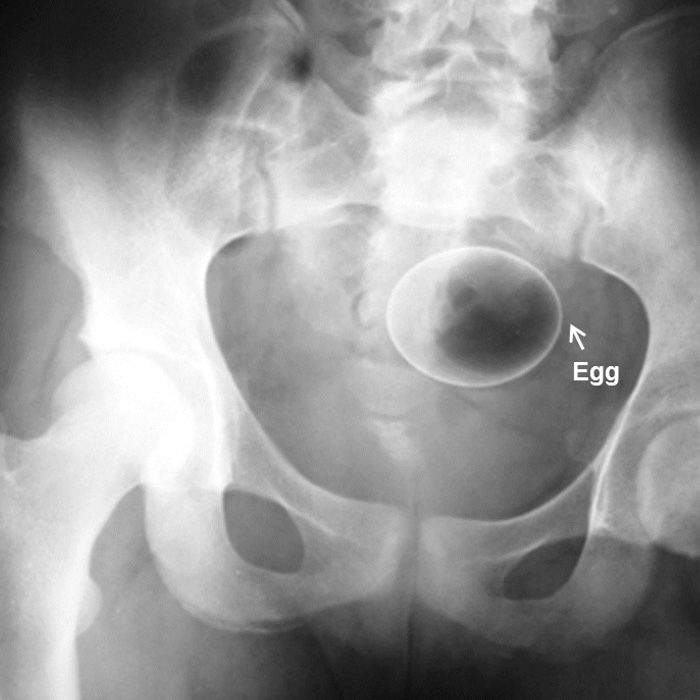

▼雞蛋這個有點厲害,難道放的過程不會不小心弄破嗎?

圖片來自:ems1